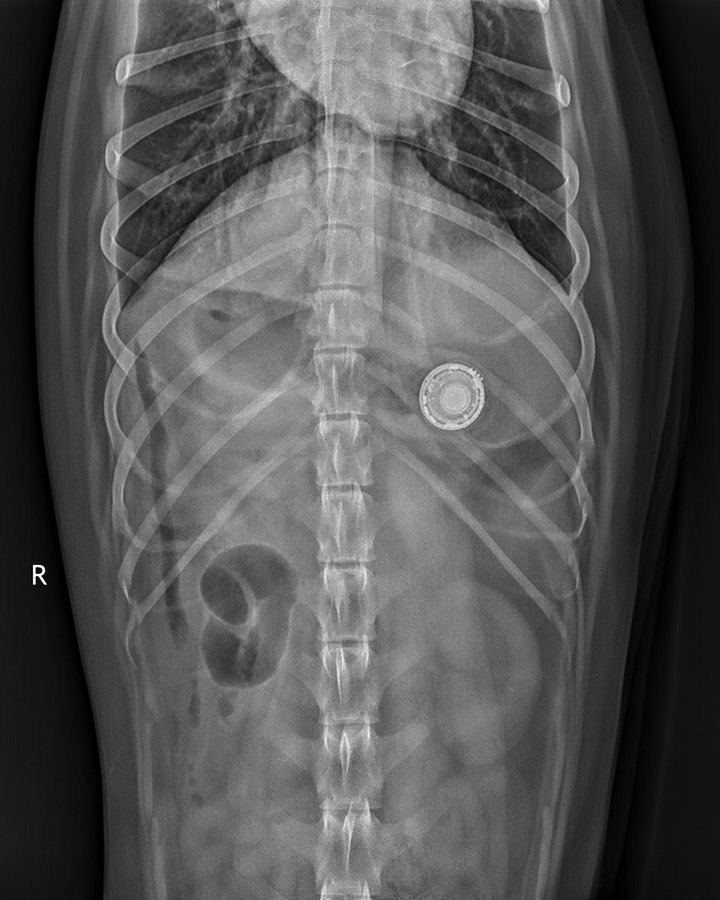

| Ảnh chụp X quang cho thấy AirTag nằm trong cơ thể chú chó. Ảnh: Schwarzman Animal Medical Center. |

Nhiều bác sĩ thú y đã cảnh báo người dùng không nên đeo AirTag vào vòng cổ thú cưng. Họ đăng tải ảnh chụp X quang ổ bụng của nhiều chú chó cho thấy chiếc AirTag xấu số nằm yên bên trong.

Thông thường, các chú chó có thể nôn hoặc thải ra bằng cách đi nặng mà không bị tổn hại gì. Tuy nhiên, trong một số trường hợp, thiết bị theo dõi của Apple có thể bị mắc kẹt nên cần phải thực hiện tiểu phẫu. Nếu ở trong bụng thú cưng quá lâu, phần pin của thiết bị có thể bị chảy, gây ra các biến chứng hay thậm chí là hủy hoại nội tạng của chúng.